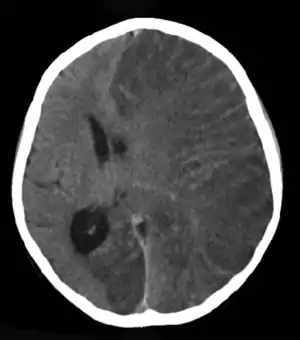

![]() | |

| Brain CT scan of a girl with Rasmussen's encephalitis. | |